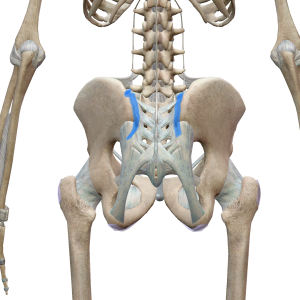

膝痛改善 堺市パーソナルトレーニング、腰痛改善、仙腸関節の簡単な調整法